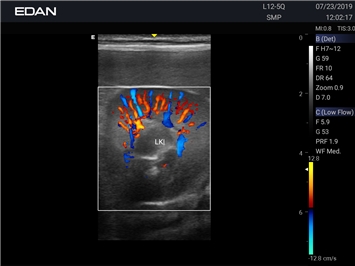

Ветеринарный ультразвук одним нажатием. Система Acclarix AX2 VET разработана с целью обеспечить бескомпромиссную производительность по доступной цене. Наличие уникальных двойных аккумуляторов в легком корпусе массой 4,5 кг из магниевого сплава позволяет системе Acclarix AX2 VET удовлетворять все потребности ветеринарных исследований, сохранив низкую стоимость.

EDAN Acclarix AX2 VET представляет собой специализированную ветеринарную ультразвуковую систему, сочетающую высокую производительность с доступной ценой. Благодаря продуманной конструкции и передовым технологиям, система обеспечивает качественную диагностику животных различных видов.

Цветовой допплер:

Да

Энергетический допплер: